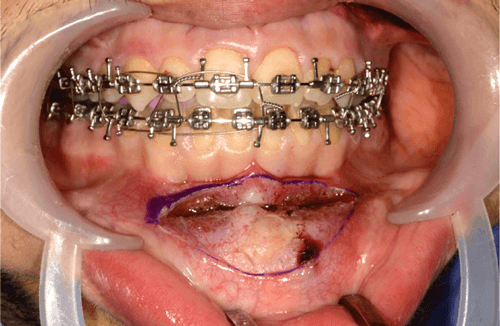

Advancement genioplasty is performed under general anaesthesia via nasotracheal intubation. The operative field is cleansed with aqueous povidine iodine (betadine) and the patient draped exposing the entire face with sterile drapes. 2% lignocaine with 1/80,000 adrenaline is infiltrated into the lower gingivobuccal sulcus to provide anaesthesia and haemostasis. We use a photographic retractor to retract the lips and make a full thickness mucoperiosteal incision from canine to canine, with an inverted ‘V’ shape to preserve the labial frenulum (Figure 1).

Figure 1.

It is crucial to leave a cuff of mentalis muscle attached to the symphysis to allow for resuspension of the muscle and avoid excessive stripping of the soft tissues to minimise the risk of inadvertent lower lip / chin ptosis and preserve blood supply to the distal osteotomised portion of the mandible. Subperiosteal dissection continues such that the entire anterior bony chin is exposed and extends laterally to identify the mental foramen and its associated neurovascular bundle. Once identified, we protect the nerve by placement of a surgical instrument positioned anterior to its exit from the foramen.